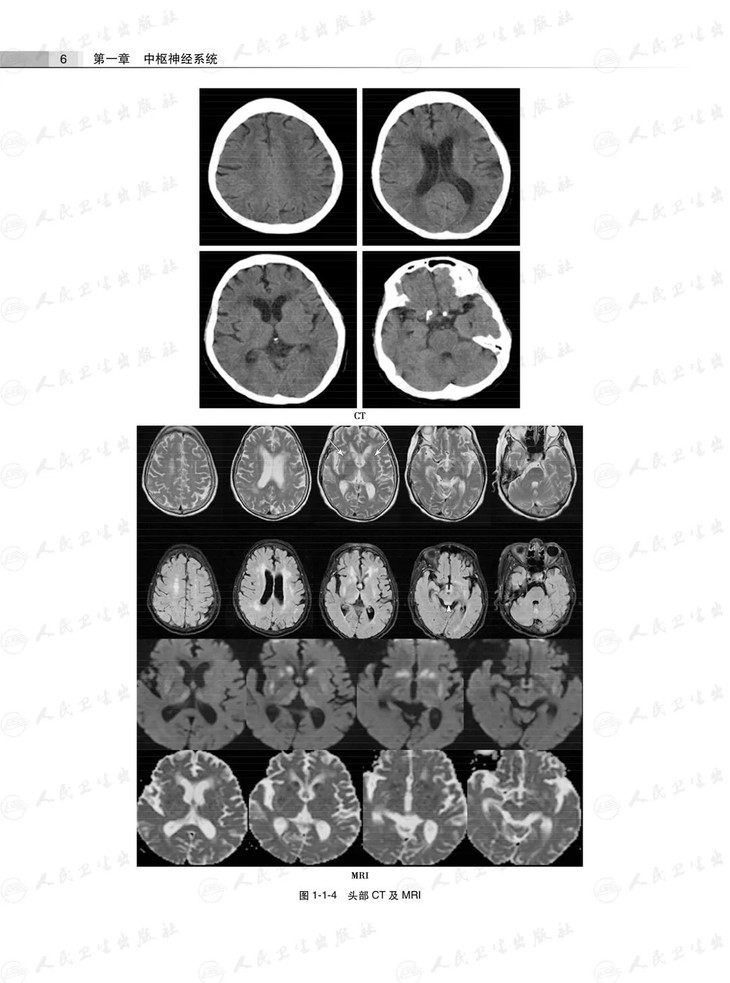

第一章中枢神经系统

第一节中毒性及营养代谢性疾病